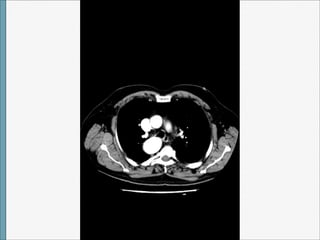

TAC

Arco Aórtico Derecho

1)CON ARTERIA SUBCLAVIA IZQUIERDA ABERRANTE

• Prevalencia:1/100. No predominio por sexo o

raza.

• Embriología: ruptura entre la arteria carótida

común izquierda y la arteria subclavia

izquierda que se origina sobre un divertículo

de Kommerell.

• Clínica: no sintomatología, hallazgo

incidental. Si presenta síntomas

relacionados con :

- Compresión esófago y tráquea por el

diverticulo o la arteria subclavia izquierda.

• -Persistencia de un ligamento arterioso

entre arteria subclavia aberrante y arteria

pulmonar.

• No relación con cardiopatía congénita